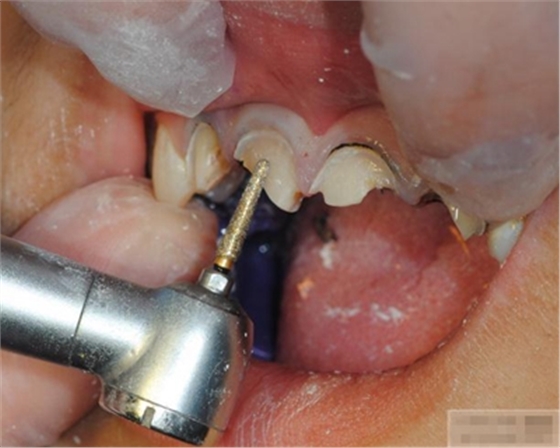

【纖維樁制作】

制作 背板

修復(fù)鄰壁

修整纖維樁長度

取出纖維樁,按所需長度裁截纖維樁 在有水條件下 用切割砂片或車針截取纖維樁,切勿使用鉗子,剪刀或鑷子以免破壞樁的結(jié)構(gòu)

涂布硅烷偶聯(lián)劑

涂布粘接劑

將樹脂粘接劑均勻涂抹在根管、牙體的粘接面以及纖維樁表面,涂抹兩遍

粘接

將調(diào)好的樹脂水門汀用口內(nèi)注射頭送入根管

將纖維樁表面涂滿調(diào)好的樹脂水門汀,安放在根管內(nèi)就位,保持壓力10秒